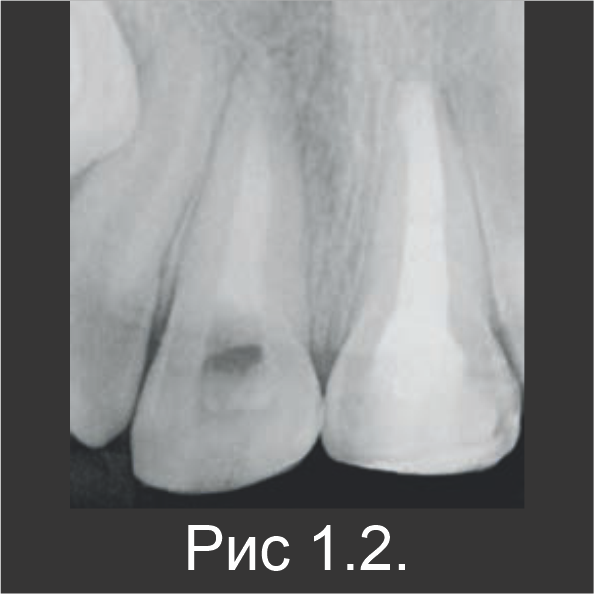

Апексифиция

9-летнюю девочку направили для лечения некроза пульпы незрелого зуба 21, который возник в результате травмы, произошедшей несколькими неделями ранее. В область травмирующего воздействия были вовлечены верхние центральные резцы 11 и 21. Когда материала Biodentine™ еще не было, для апексификации в качестве пробки использовали МТА, а поверх нее нанесли гуттаперчу (рис. 1.1). Через три месяца в зубе 11 также обнаружили некроз пульпы. После стандартного промывания канала гипохлоритом натрия без обработки инструментами, зуб 11 запломбировали гидроксидом кальция и оставили на 1 неделю, чтобы затем выполнить лечение с использованием Biodentine™. В течение второго визита эндодонтический канал запломбировали материалом Biodentine™ по всей длине (рис. 1.2).

Сообщений о постоперационной боли не было. По истечении 6-месячного периода наблюдения патологии на рентгенограмме не наблюдались (рис. 1.3). Клинически в зубе 21, который лечили с использованием МТА, определялось небольшое изменение цвета (рис. 1.4). Известно, что MTA может повлечь изменение цвета коронки, а в данном случае – вероятно, из-за остатков МТА в пришеечной зоне. Патологий в апикальной зоне обоих резцов обнаружено не было.